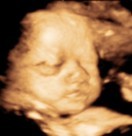

มาอวดรูปตอนซาวด์กันหน่อยค่ะ แม่ๆกำหนดคลอดเดือนไหนบ้างคะ